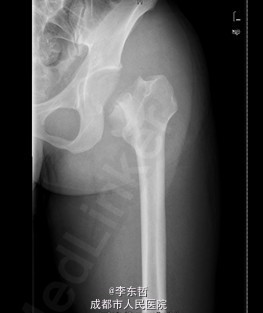

患者男,31岁,因“左股骨头股骨颈骨折切开复位内固定术后1+年”入院。患者1+年前因车祸致左股骨头、颈粉碎性骨折伴坐骨神经损伤于我院就诊,于我院行左股骨头股骨颈骨折切开复位空心钉+可吸收镙钉内固定术,术后恢复良好出院。术后8月后扶双拐活动。7月前患者无明显诱因出现左髋部疼痛,以负重时为重,后患者只能扶双拐活动。现患者为进一步治疗入我院。患病以来患者精神可,食欲可,睡眠可,大小便未见明显异常,体重无明显变化。

查体:T:36.2oC,P:80次/分,R:20次/分,BP:112/74mmHg。神志清楚,无病容,皮肤巩膜无黄染,全身浅表淋巴结未见肿大。颈静脉搏动、心界正常,心律齐,各瓣膜区未闻及杂音。胸廓未见异常,双肺叩诊呈清音,双肺呼吸音清,未闻及干湿啰音及胸膜摩擦音。腹部外形正常,全腹柔软,无压痛及反跳痛,腹部未触及包块,肝脏肋下未触及,脾脏肋下未触及,双肾未触及。双下肢无水肿。视:左髋外侧可见一约30cm手术瘢痕,其上可见一点状结痂,左腿较右腿短缩,左腿肌肉较右腿萎缩,步态异常。触:左髋部无压痛,左腿外侧感觉异常,以左膝外侧为重,左髋外侧叩击痛,左足背动脉搏动未扪及异常。动量:左下肢较右下肢短缩约3cm,左髋关节活动受限,其余各关节未见明显异常。

入院诊断:左股骨头股骨颈粉碎性骨折切开复位内固定术后坏死;积极完善术前检查及准备后行关节置换术。